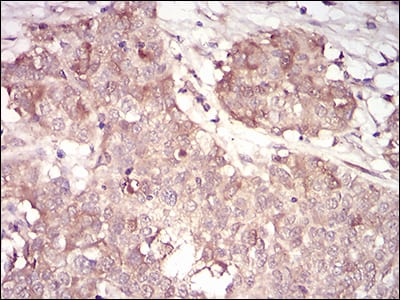

Immunohistochemical analysis of paraffin-embedded human cervical cancer tissues using CCNA2 mouse mAb with DAB staining.

Immunohistochemical analysis of paraffin-embedded human bladder cancer tissues using CCNA2 mouse mAb with DAB staining.